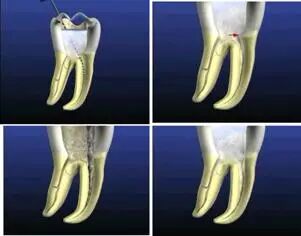

根管治疗术是医生用根管治疗专用器械通过彻底去除感染的牙髓以及感染的牙本质和毒性分解产物,经过根管冲洗、消毒和严密填塞根管,隔绝细菌进入根管再感染,防止根尖周病变的发生或促进根尖周病的愈合。

1、开髓去腐质

根管治疗开髓前必须去净腐质,然后换用另一根新的车针(裂钻或金刚砂车针均可,但金刚砂车针开髓震动感少,开髓稳)进入髓腔,穿通髓腔后换高速球钻揭顶,揭顶一定要全,以能看清整个髓室底为准,然后换用裂钻或金刚砂车针修整髓壁。

这一步质控的标准是:

①去净腐质和原有充填物。

②揭净髓顶,看到整个髓底解剖结构。

③髓壁与根管壁连续流畅。

④没有牙颈部台阶,没有过度切割髓壁和髓底。